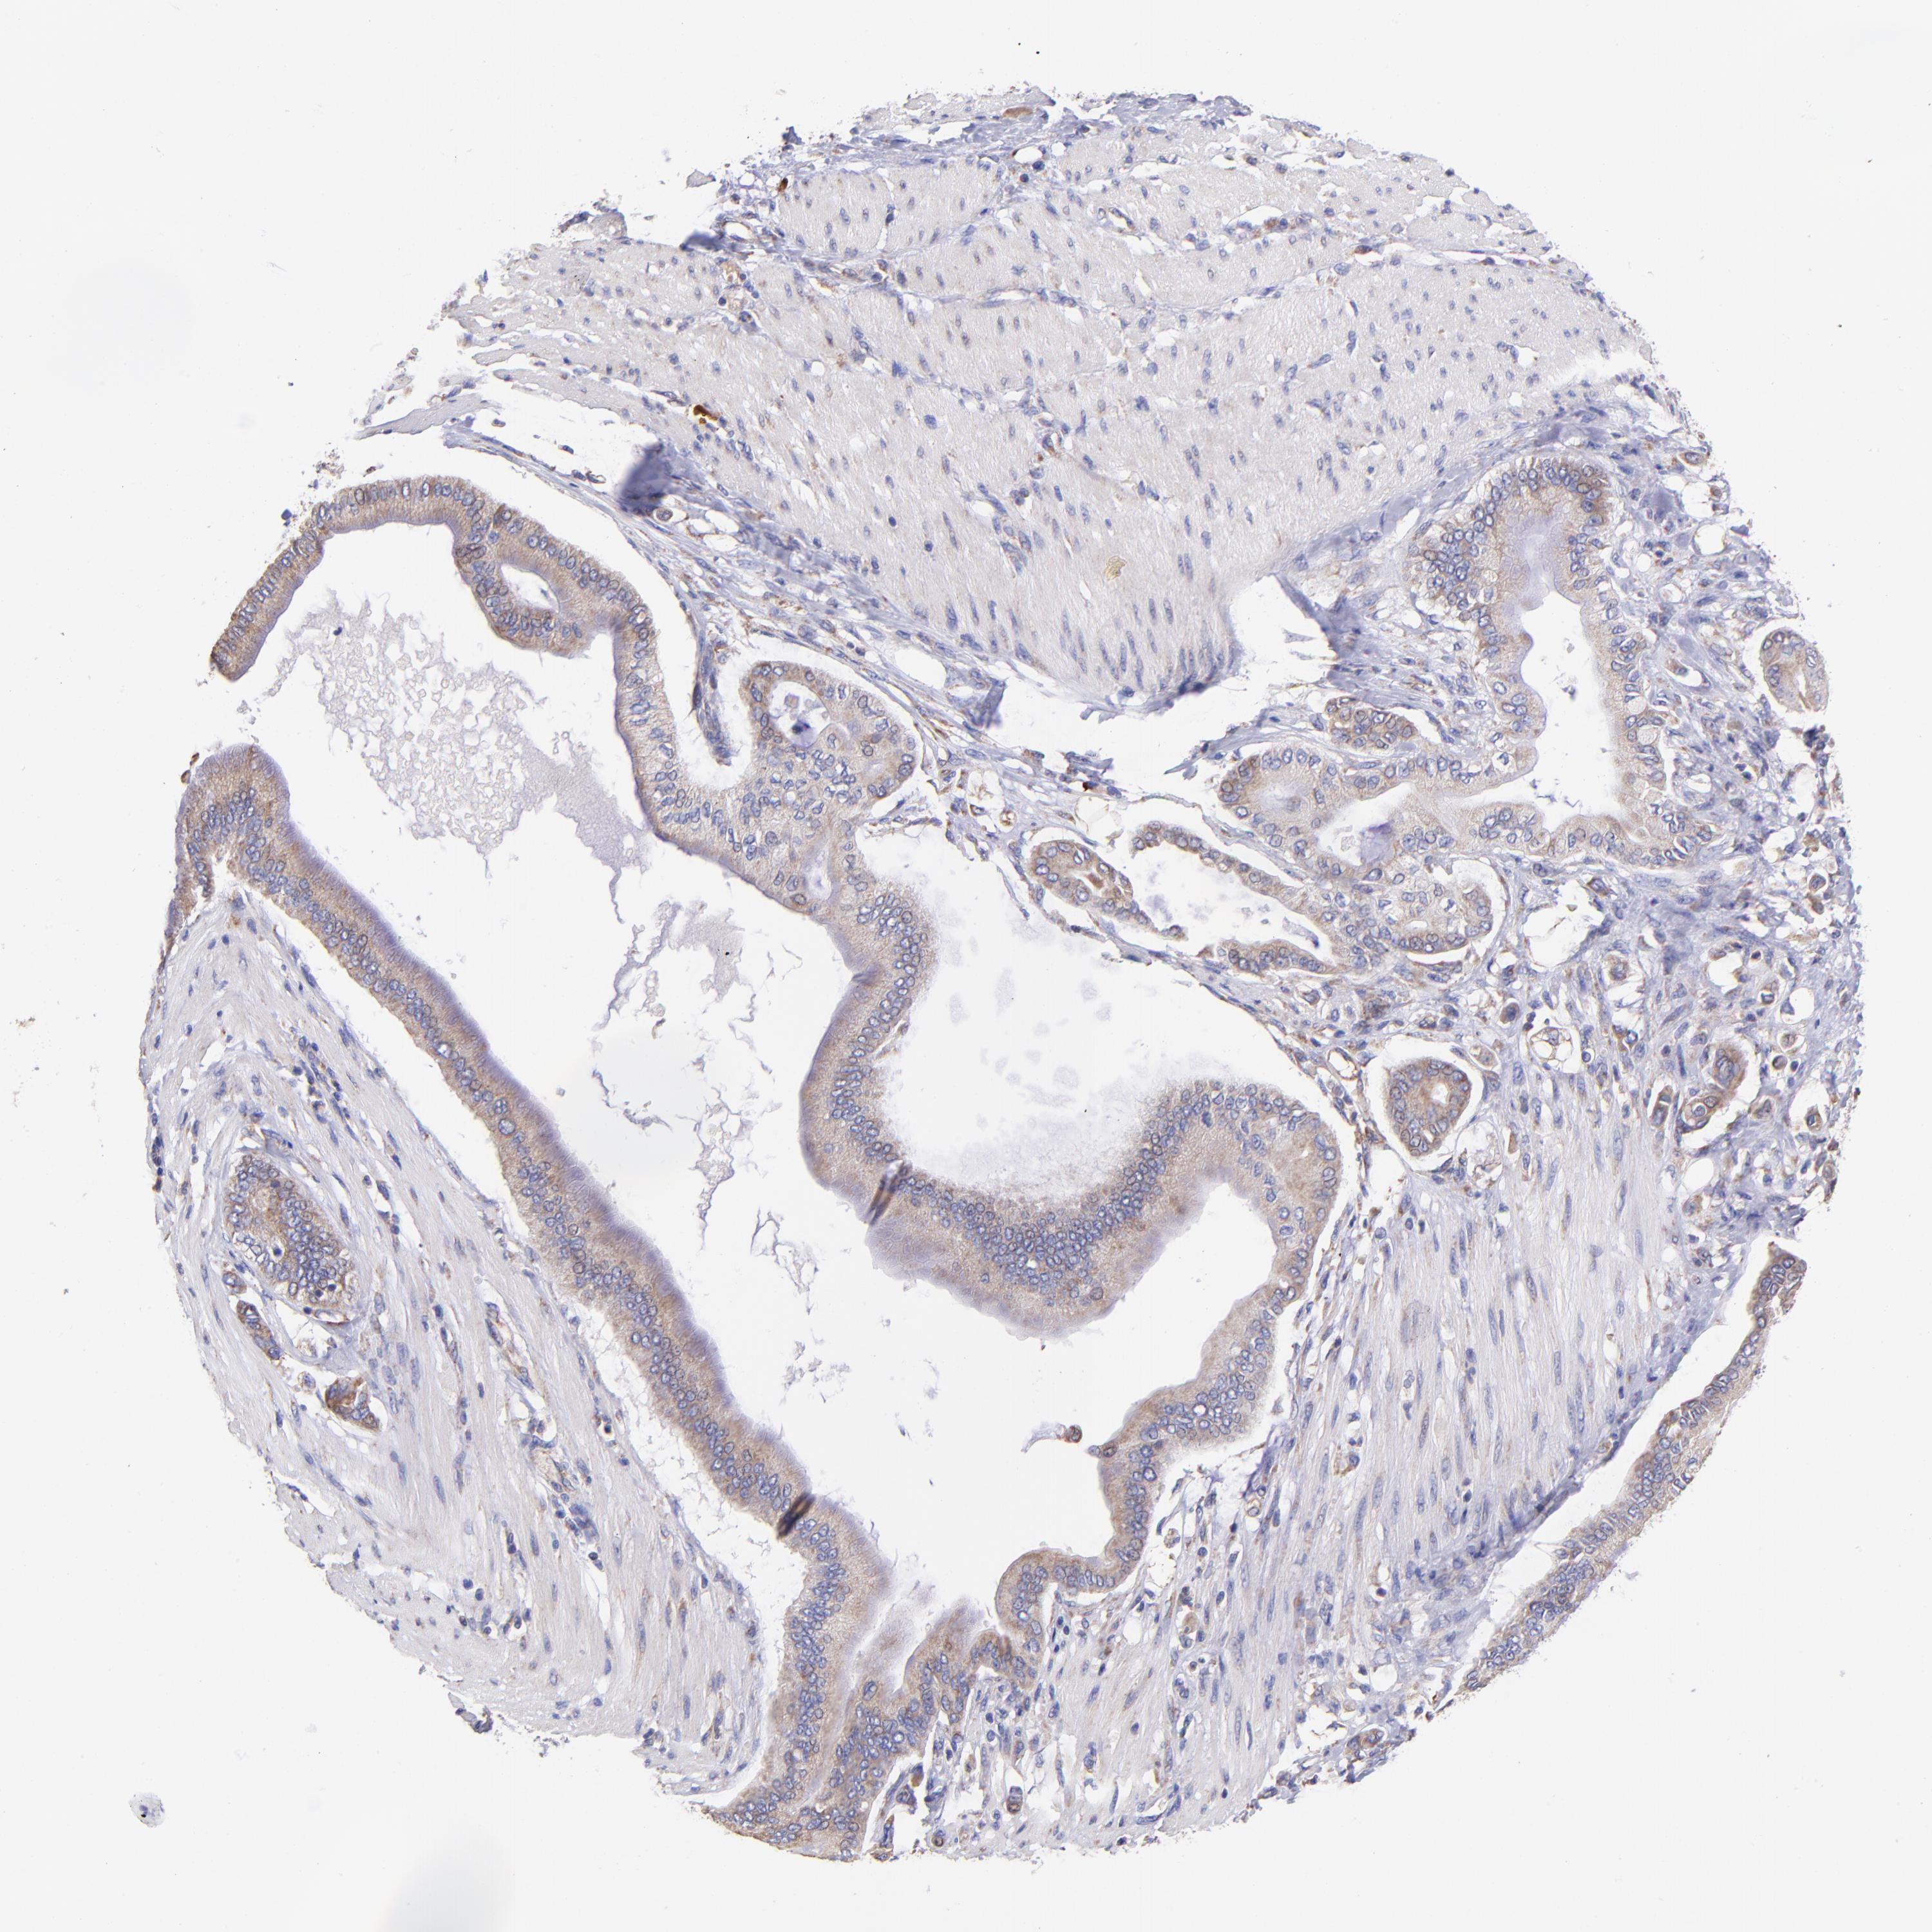

PANCREATIC CANCER - Protein expressioni

A mouse-over function shows sample information and annotation data. Click on an image to view it in a full screen mode. Samples can be filtered based on level of antibody staining by selecting one or several of the following categories: high, medium, low and not detected. The assay and annotation is described here.

Note that samples used for immunohistochemistry by the Human Protein Atlas do not correspond to samples in the TCGA dataset.

Antibody stainingi

Antibody staining in the annotated cell types in the current human tissue is reported as not detected, low, medium, or high, based on conventional immunohistochemistry profiling in selected tissues. This score is based on the combination of the staining intensity and fraction of stained cells.

Each image is clickable and will lead to virtual microscopy that enables deeper exploration of all samples and also displays staining intensity scores, fraction scores and subcellular localization as well as patient and tissue information for each sample.

Antibody HPA001927

Staining

High

Medium

Low

Not detected

Intensity

Strong

Moderate

Weak

Negative

Quantity

>75%

75%-25%

<25%

None

Location

Nuclear

Cytoplasmic/membranous

Cytoplasmic/membranous,nuclear

Adenocarcinoma, NOS

Adenocarcinoma, metastatic, NOS